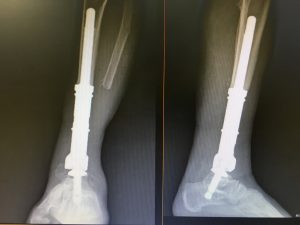

Prótesis tumorales (megaprótesis)

Diseñadas para sustituir grandes segmentos óseos resecados por tumores, generalmente en extremidades largas como fémur, húmero o tibia. Son altamente personalizadas.